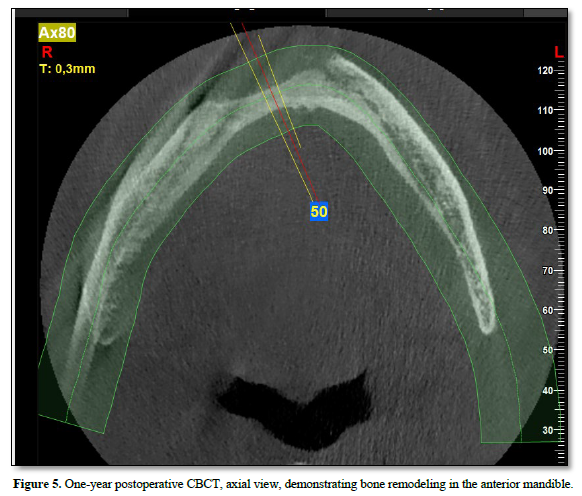

At the one‑year follow‑up, intraoral examination showed complete mucosal healing (Figure 11). CBCT acquired at the same visit—axial, sagittal, and frontal views plus three‑dimensional reconstruction—demonstrated stable bone remodeling of the anterior mandible (Figures 5–8). A one-year postoperative panoramic radiograph also confirmed preserved mandibular continuity, absence of recurrent pathology, and satisfactory bone healing (Figure 12).